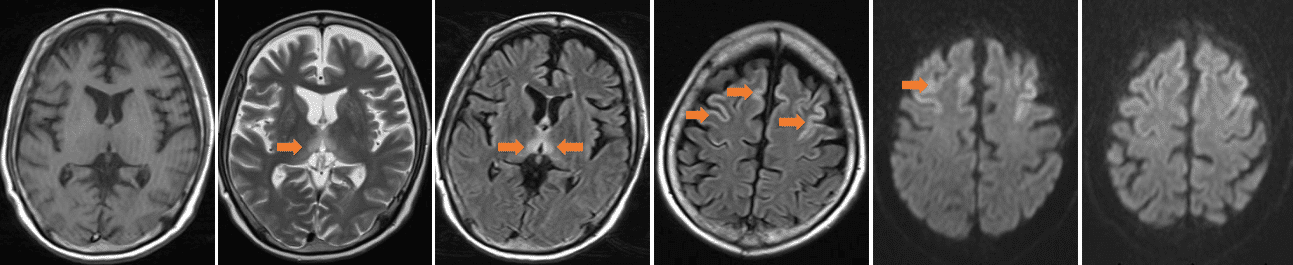

头MR(2024-3-17) :双侧丘脑及双侧额叶皮层见多发对称性长T1长T2信号,FLAIR像为高信号,DWI上病变呈高信号影,ADC上病变呈等信号影。 影像结果:双侧丘脑及双侧额叶皮层对称性异常信号,建议进一步检查。